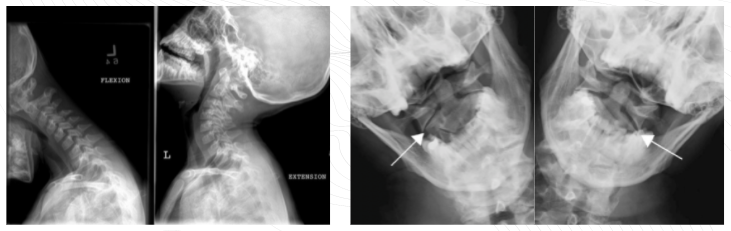

AO dislocation types? mechanism?

_Type 1_ common **ventral dislocation** _type II_ highly unstable **longitudinal distractions** (upward force) _type III_ rarest **dorsal dislocation** mechanism = **hyperextension** trauma to posterior AO (tectorial) membrane + lateral flexion

C1 fracture Ax? types?

axial loading (force directed through top of the head → through spine) due to RTA ## Footnote _jefferson fracture/burst fracture_ = anterior + posterior arches of C1 atlas (occipital condyles press onto lateral masses causing breakage of A + P arches) _posterior arch fracture_ = related to hyperextension _anterior arch fracture_ = hyperflexion _lateral mass fracture_ = lateral flexion on one side of vertebrae (**note: burst + lateral mass fractures both involve rupture of transverse ligament)**

27

ewrbe

A = jefferson fracture B = lateral mass fracture C = lateral mass fracture